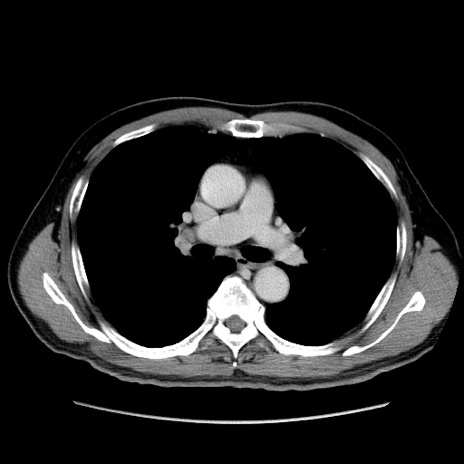

症例34(横断像)

【症例】60歳代 男性

【主訴】右鼠径部膨隆

【現病歴】1年程前より右鼠径部膨隆あり。自己にて還納可能だったため放置していた。3時間前より右鼠径部の脱出を認め、還納困難となり受診。

【身体所見】右鼠径部に小児頭大の膨隆あり。弾性硬であり、用手還納は困難。左鼠径部にも膨隆を認める。脱出はなし。